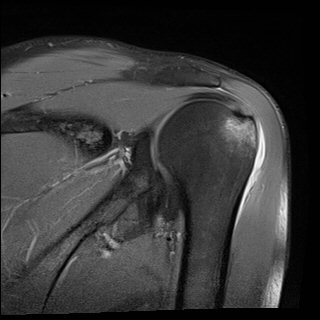

ÀÚ±â°ø¸í°Ë»ç

»ó¿Ï°ñµÎ ´ë°áÀý °ß¿­°ñÀý